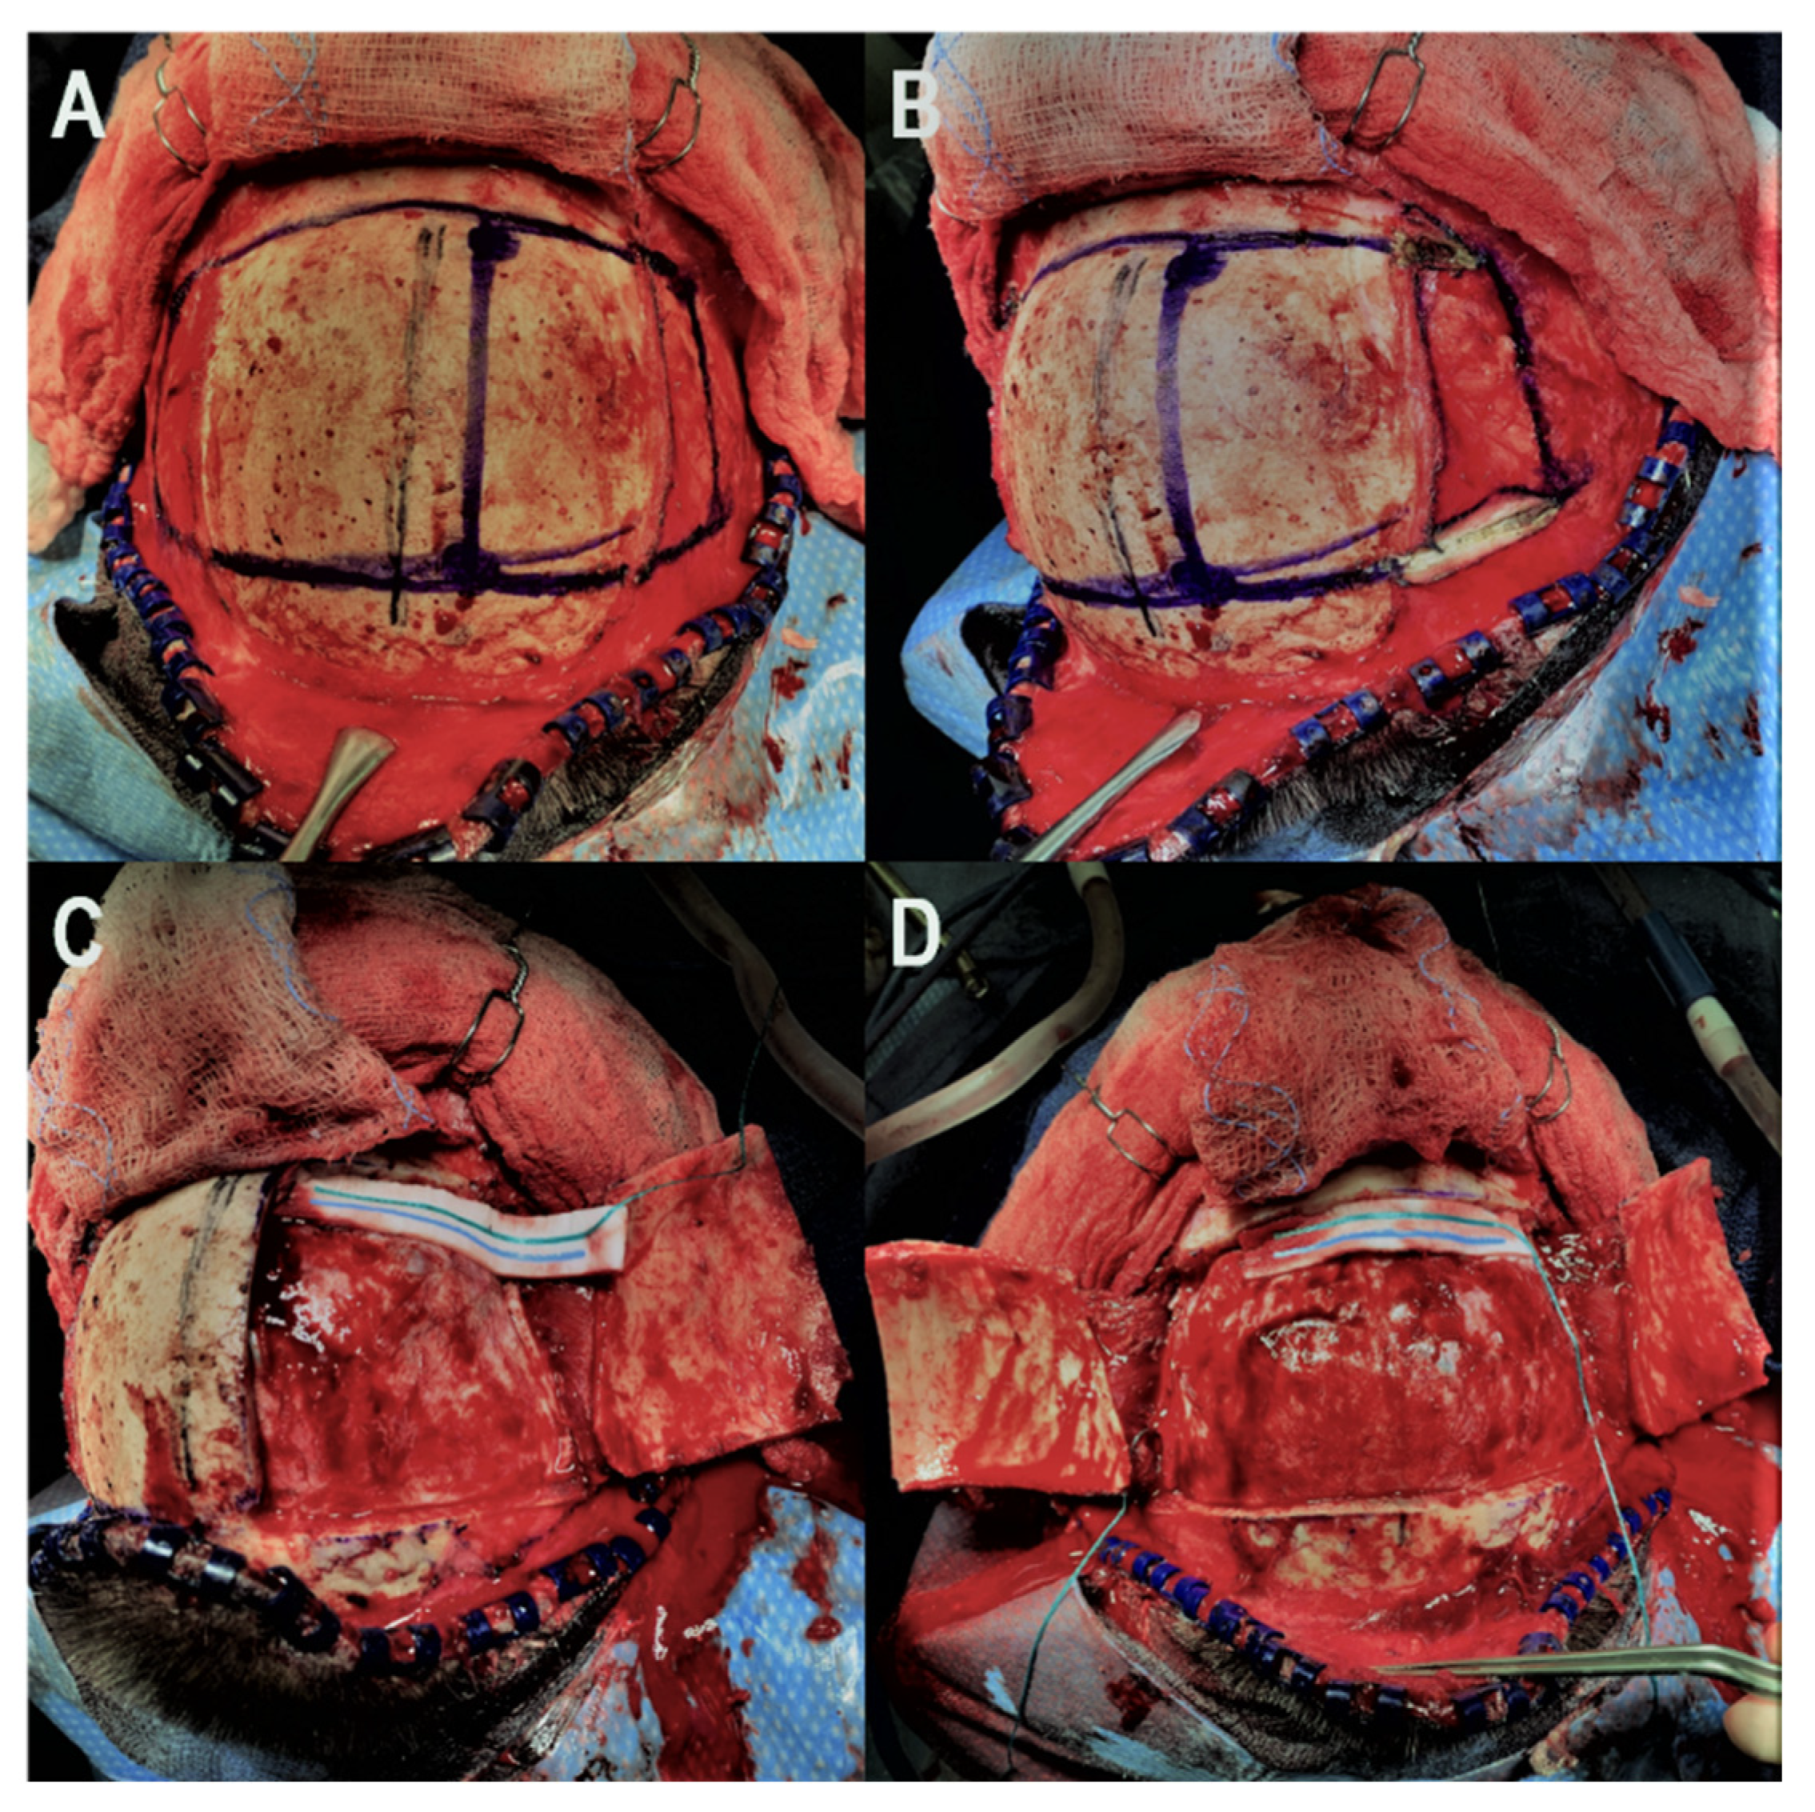

Our technique for performing the bifrontal osteoplastic flap is illustrated in

Figure 1. A standard bicoronal incision is performed, followed by subgaleal dissection and harvest of a vascularized pericranial graft. The pericranial graft is harvested as large as possible, limited laterally by the temporalis muscle bilaterally, superiorly about 1–2 cm posterior to the posterior scalp flap, and anteriorly down to the superior orbital rim. At this point, the midline is identified based on the location of the sagittal suture, and 6 burr holes are marked (

Figure 1A). The first two burr holes are marked on the right side about 2 cm lateral to the midline. The anterior burr hole is marked just posterior to the superior orbital rim and the posterior burr hole is marked just anterior to the coronal suture. By keeping the burr holes 2 cm lateral to the midline, we minimize the chances of inadvertent injury to the superior sagittal sinus during drilling. Two burr holes are then marked on each temporalis muscle, the anterior one at the keyhole and the posterior one at a point where a 90-degree angle is created between a line that connects this burr hole to the keyhole burr hole and another line that connects it to the posterior paramedian burr hole. Following this, monopolar electrocautery is used to cut the temporalis muscle areas anteriorly and posteriorly where the burr holes are marked (

Figure 1B) bilaterally. The burr holes are then drilled and connected first on the right side in order to elevate the right-sided osteoplastic flap (

Figure 1C). The temporalis muscle must be undermined posterior to the keyhole burr hole and anterior to the posterior temporalis burr hole so that the osteotome can be angled superiorly while connecting these two burr holes in order to extend the amount of bone that can be drilled under the muscle. If the bone cuts cannot be fully connected under the temporalis muscle, the bone flap can be epidurally dissected from medial to lateral and then fractured at its base under the temporalis muscle. At this point, the superior sagittal sinus can be epidurally dissected from lateral to medial and the same process is repeated on the left side to elevate the left-sided osteoplastic flap, completing the bifrontal osteoplastic flap (

Figure 1D). Avoidance of damaging the temporalis muscle with the drill is important, as is avoiding excessive subperiosteal dissection while performing the above-mentioned steps, as this would render the osteoplastic flap ineffective. For reconstruction, we prefer one small dog bone just medial to each keyhole burr hole, one small dog bone to connect the bone flaps and a burr hole cover at the most posterior paramedian burr hole (